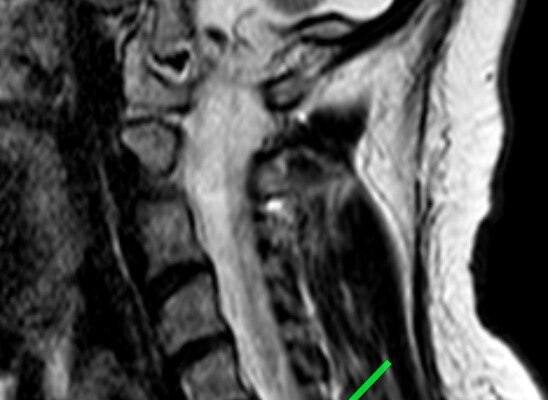

Пациентка обратилась с жлобами на изматывающую боль в руке. Ей провели МРТ, которое показало, что в шейном отделе сформировалась грыжа размером 8 мм. По словам медиков, образование сдавливало спинномозговой канал и корешковое отверстие, угрожая двигательной функции.

«Мы провели сложнейшее микрохирургическое вмешательство, в ходе которого удалили грыжу и стабилизировали позвоночник с помощью современного импланта», — рассказал нейрохирург Николай Карпов, отметив, что операция длилась два часа 20 минут.